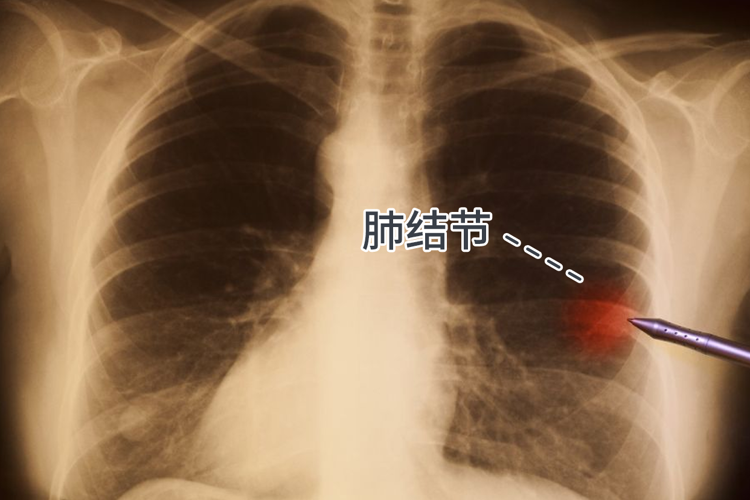

肺结节:肺部影像显示直径的类圆形、局灶性且密度增高的实性、亚实性肺部阴影 , 有95%以上为良性 , 不需要敢干预治疗 。 针对<5mm肺小结节定期复查即可 , 而5-10mm肺小结节则需密切随访 , 而≥10mm肺结节则要重视并尽早治疗 。